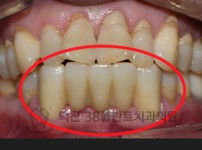

치료전후